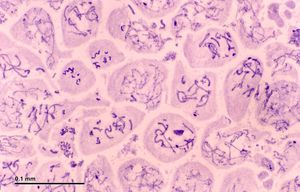

الخلية النطفية Spermatocytes are a type of male gametocyte in animals. They derive from immature germ cells called spermatogonia. They are found in the testis, in a structure known as the seminiferous tubules.[1] There are two types of spermatocytes, primary and secondary spermatocytes (Figure 1). Primary and secondary spermatocytes are formed through the process of spermatocytogenesis (Figure 3).[2]

Histological section through testicular parenchyma of a boar. 1 Lumen of Tubulus seminiferus contortus, 2 spermatids, 3 spermatocytes, 4 spermatogonia, 5 Sertoli cell, 6 Myofibroblasts, 7 Leydig cells, 8 capillaries